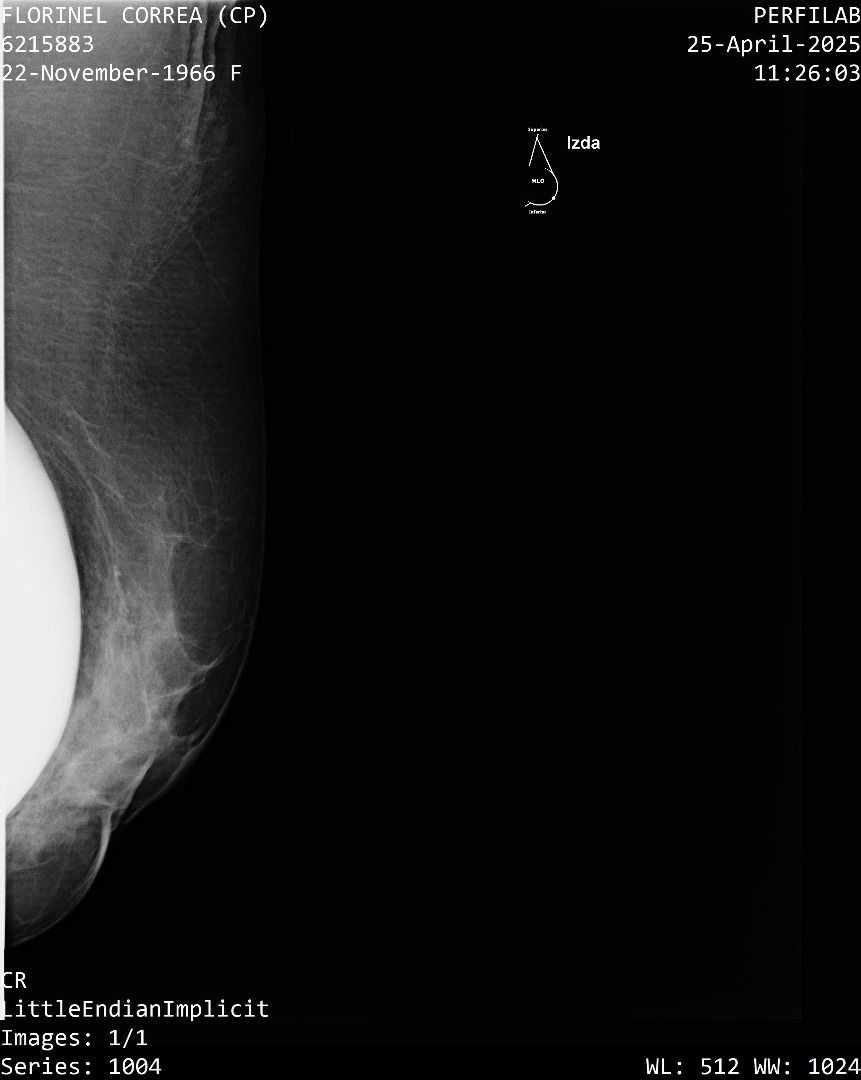

A Correa se le practicó un estudio de mamografía bilateral, la cual reporta una densidad mamaria heterogéneamente densa (ACR C), lo cual puede dificultar la detección de lesiones sospechosas.

Además, la presencia de implantes mamarios limita aún más la visibilidad del tejido mamario.

También se identificó un ganglio linfático de aspecto residual en la axila derecha que se considera sospechoso con este método, requiere evaluación urgente mediante ecografía mamaria.